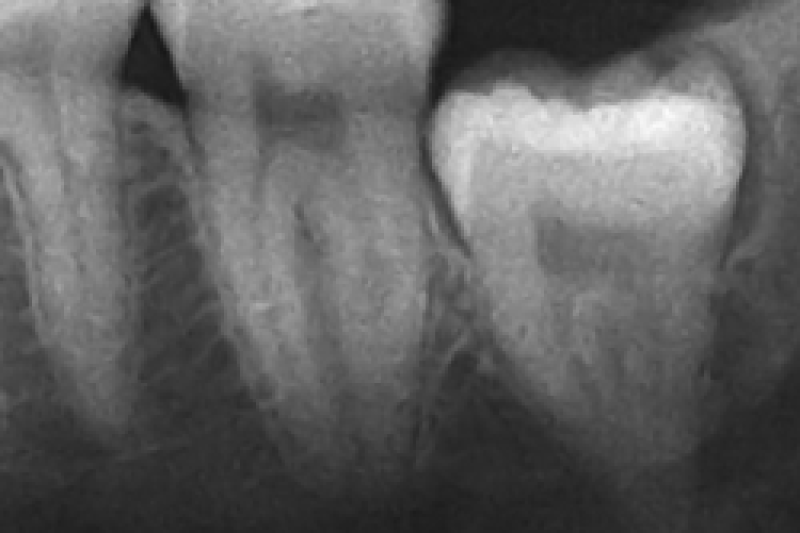

The Importance of Removing Bad Teeth to Prevent Infections

Maintaining oral health is essential for overall well-being. Neglecting dental issues can lead to severe consequences, including infections that can spread beyond the mouth. At Corona Oral Surgery and …